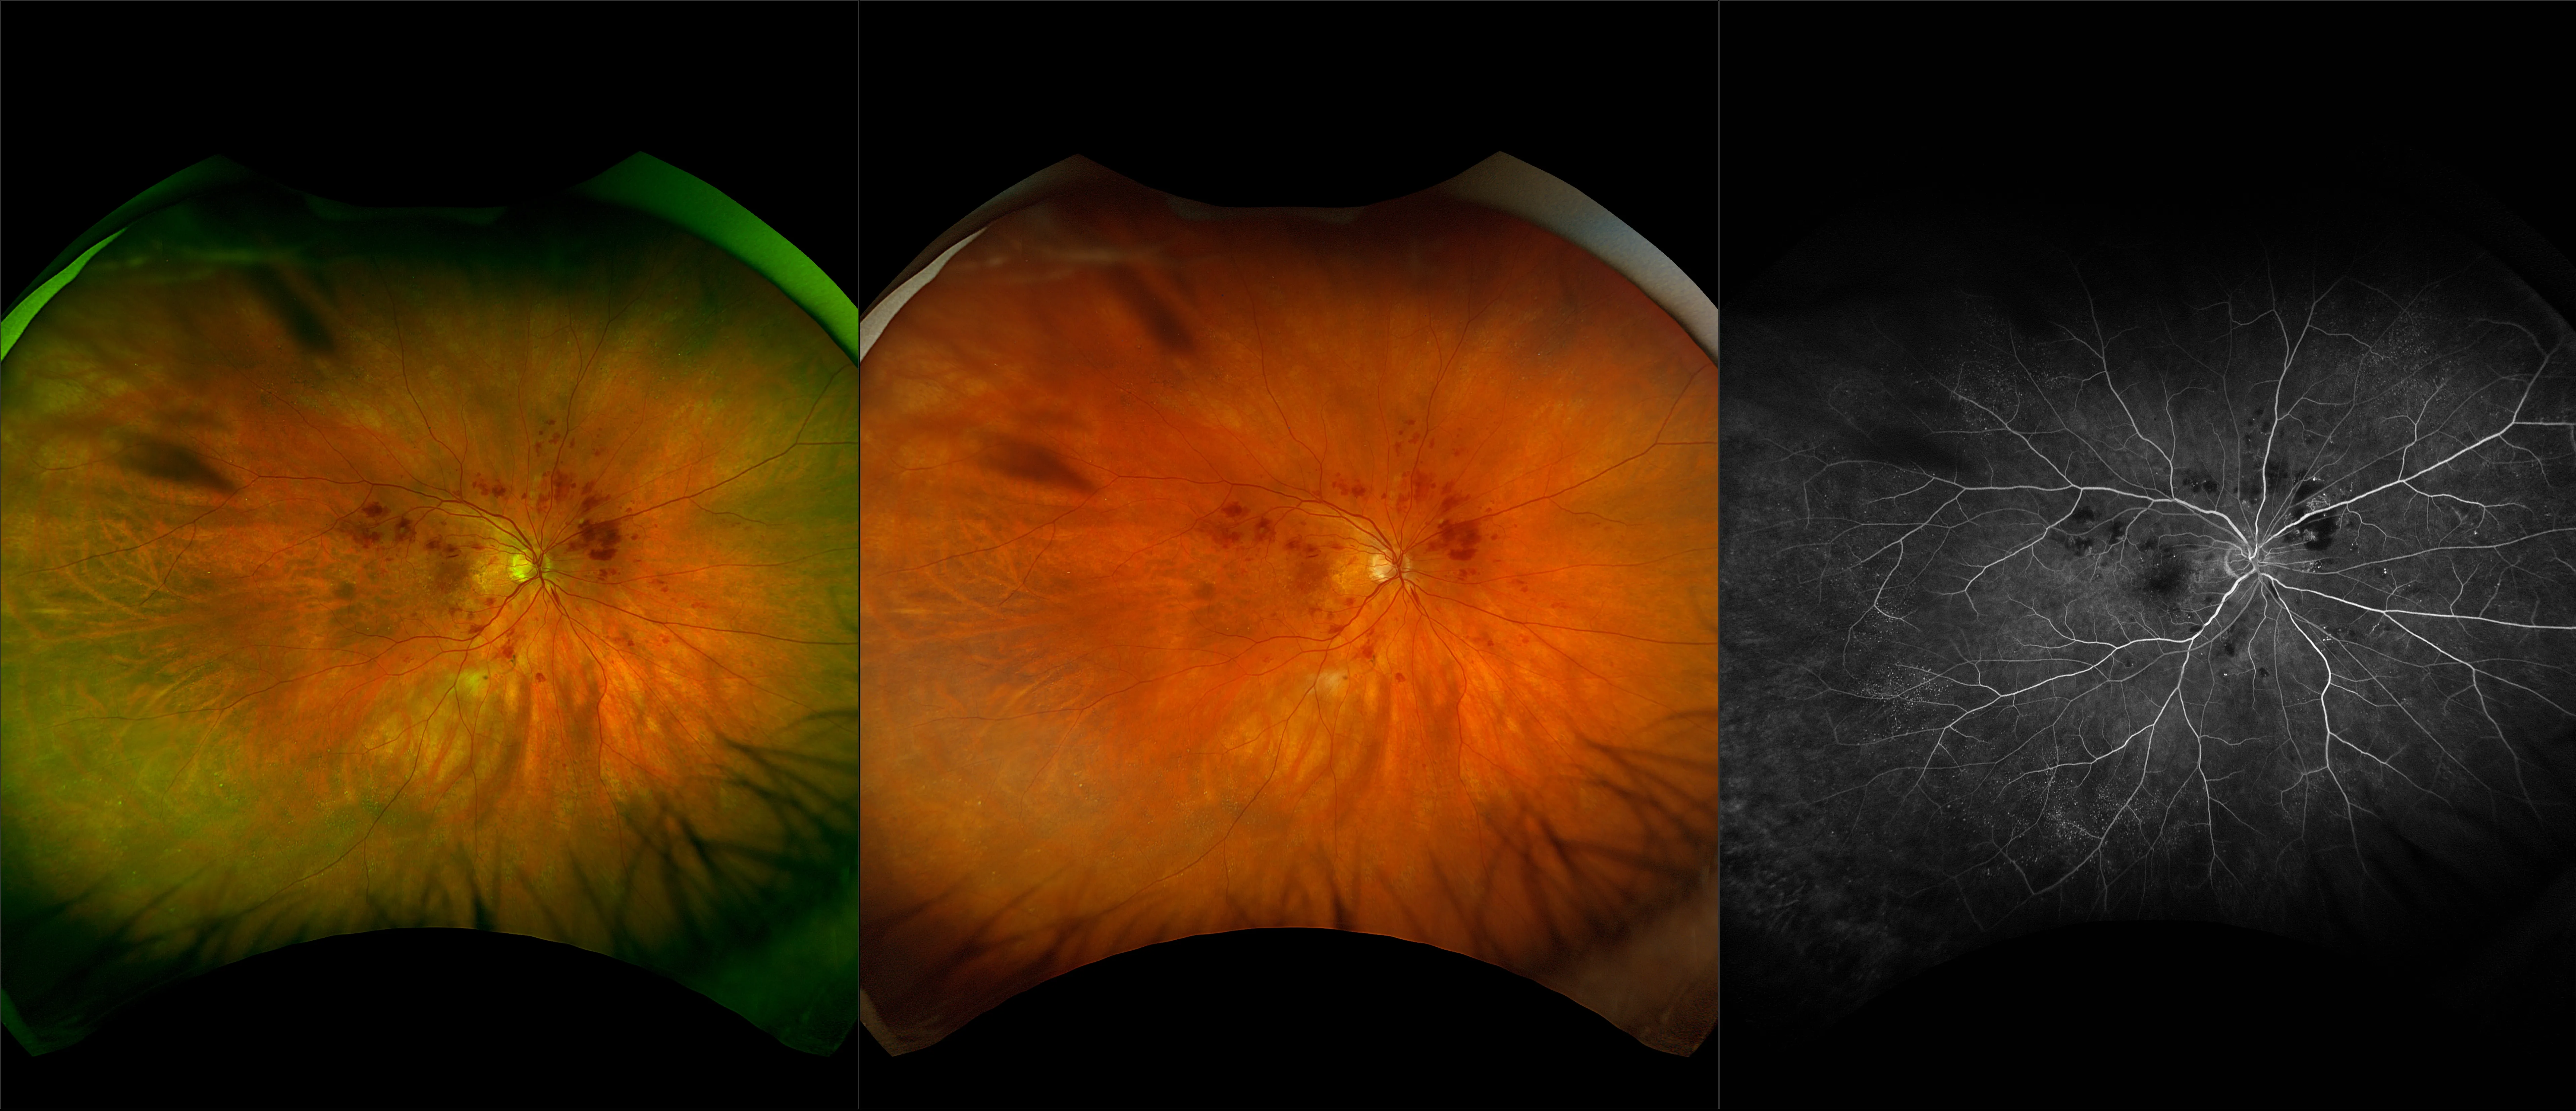

optomap® Recognizing Pathology

This material is designed as a searchable reference resource to support clinical decision-making. The information contained here should be used as general guidance when viewing optomap and OCT images from Optos devices. The differential diagnosis should be made under the direction of the responsible physician. These images were taken on the latest ultra-widefield optomap devices.

The Cases and Images

optomap Recognizing Pathology is searchable by pathology and/or optomap image modality. You may search by multiples of each selection. Each individual case is represented by the accompanying thumbnail image. Most cases include several different optomap image modalities. To view a full description of the case, please click on the thumbnail. Each image in the case will be made available through our OptosAdvance software which provides multi-dimensional visualization of digital images to aid in the analysis of anatomy and pathology. Support and pathology definitions can be found by selecting one of the buttons, above. Should you have questions, please complete the form below.